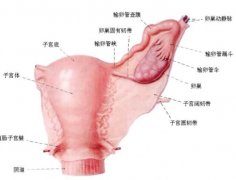

已经8个月了,医生建议可以去做个胎儿心脏检查,是四维彩超,不知道是不是只要是8--9个月之间都可以,会不会对胎儿有影响!

怀孕六个月做四维彩超发现胎儿左侧眼球内下 怀孕八个月做四维彩超显示胎儿双顶径只有6 我现在怀孕五个月做四维彩超结果说小孩8两 怀孕六个月做四维彩超一切正常就

怀孕八个月做四维彩超显示胎儿双顶径只有6.9cm,股骨长5,7cm,双顶径太小了怎么办? 怀孕八个月做四维彩超显示胎儿双顶径只有6.9cm,股骨长5,7cm,双顶径太